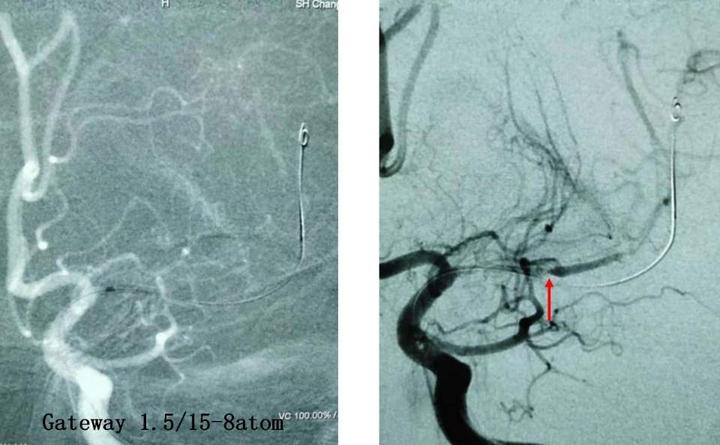

3、左侧豆纹动脉显影及灌注明显改善,降低了再次基底节区脑梗塞的风险